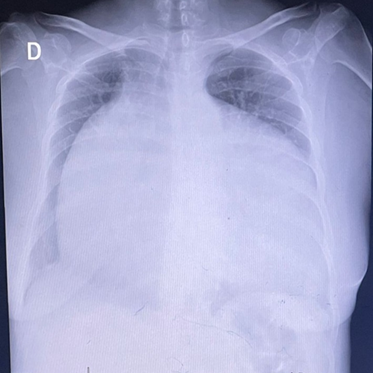

Exámenes complementarios: Electrocardiograma, evidencia fibrilación auricular, bloqueo completo de rama derecha, trastorno de la repolarización ventricular, Figura 1. Ecocardiograma reporta FEVI: 39%, rectificación del septo interventricular por sobrecarga de cámaras derechas, aumento del volumen atrial derecho, discreta estenosis mitral, válvula tricúspide de implantación baja, anomalía de Ebstein, reflujo tricúspide importante, hipertensión pulmonar moderada, formen oval patente, Figura 2. Radiografía con proyección posteroanterior de tórax reveló cardiomegalia grado IV, Figura 3. Ecografía de Abdomen, concluye dilatación de las venas hepáticas secundario a falla cardíaca congestiva, asociado a leves cambios en la eco textura del parénquima hepático por lo que se debería considerar hepatopatía congestiva, además de colelitiasis, Figura 4.

Figura 3 Radiografía de tórax. archivo de la paciente. Cardiomegalia Grado IV

Es imperativo realizar un abordaje integral del paciente tomando en consideración aspectos como las comorbilidades, examen físico y exámenes complementarios que permitan definir un adecuado abordaje terapéutico, pudiendo ser farmacológico con terapia expectante y vigilancia periódica, lo cual podría ser recomendable en aquellos pacientes asintomáticos (17). No obstante, existe evidencia que sugiere un tratamiento quirúrgico temprano antes de que el cuadro se exacerbe y agrave el pronóstico del paciente (18). Con respecto a nuestro caso la paciente desarrolló complicaciones como una insuficiencia cardíaca congestiva, con una cardiomegalia grado IV por radiografía de tórax además de congestion vascular a nivel pulmonar y hepático.